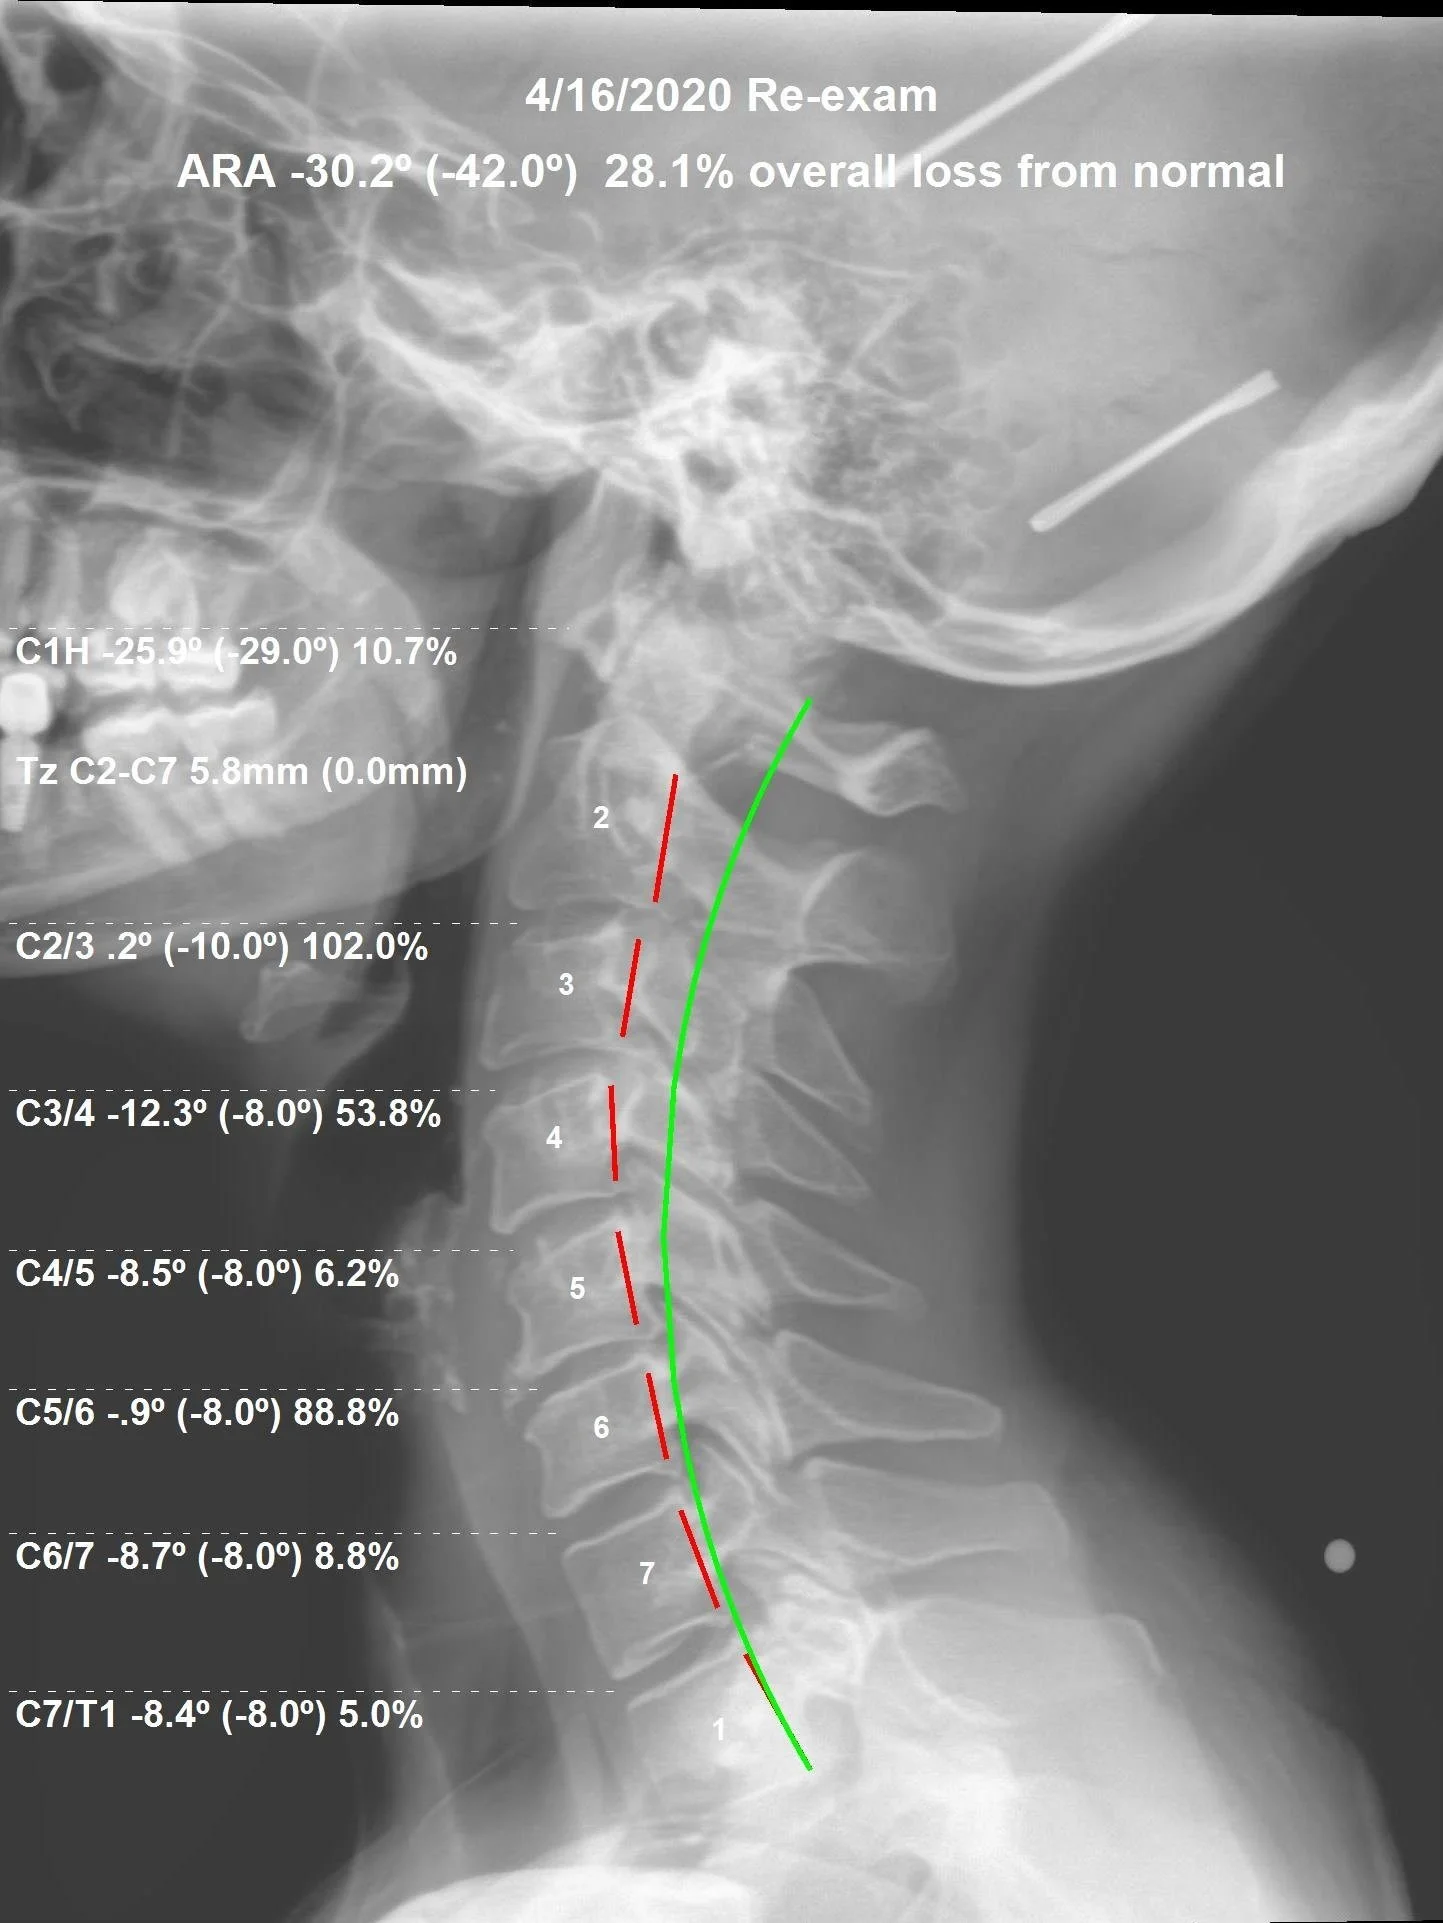

Correction of the Month